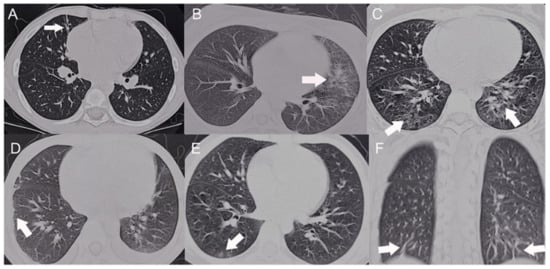

| CT | 70% of the patients showed abnormal findings such as interlobular septa thickening, parenchymal bands, etc [67]. | CT imaging is useful to make an early diagnosis of pulmonary involvement, and it provides precise expectation of pulmonary function [64]. | [67,68,70] |